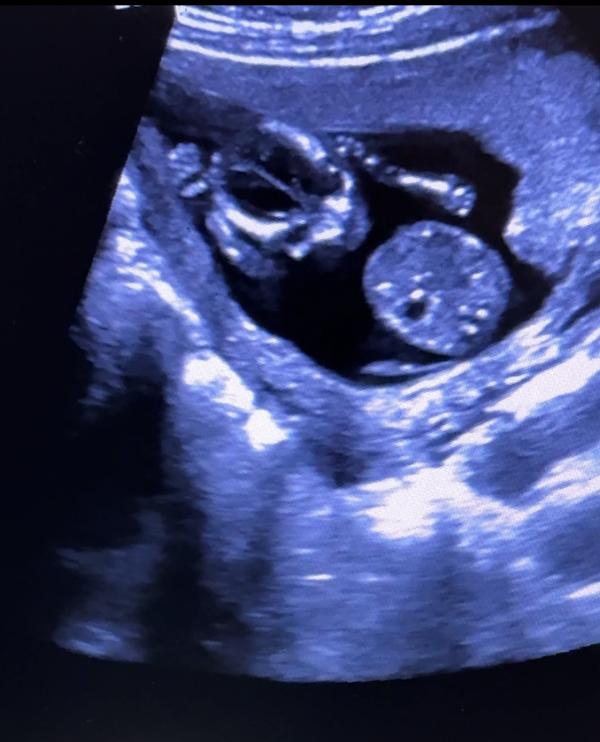

Повидались с доченькой. Ручкой помахала, спинку повыгибала, уже трогает мои стеночки. Жаль пока не ощущается. Хотя иногда есть такое чувство😇